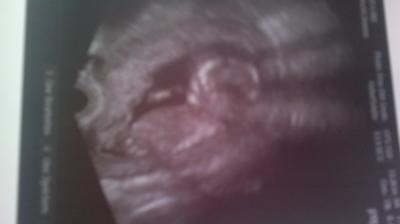

So ihr lieben i bin So Glücklich baby geht es gut und Bewegte sich die ganze Zeit beim gucken.arme und Beine alles dran und HerzChen klopft auch:) bin So froh das alles supi ist:-) Freu Freu. Hänge ein aktuelles Bild mit ran:-)

Bild zu wieder da vom fa - Forum für Juli - Mamis